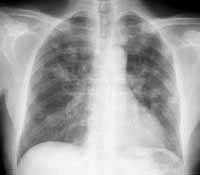

Безусловно, такие морфологические изменения, как число очагов, форма, размеры, интенсивность, структура, контуры, хорошо определяются, так как пространственное разрешение с учетом проекционного увеличения изображения составляет 0,5 мм (1 пара линий/мм.) (Рис. 1, 2).

Рис. 1. Количество, величина, форма, интенсивность, структура и контуры патологических образований хорошо определяются.